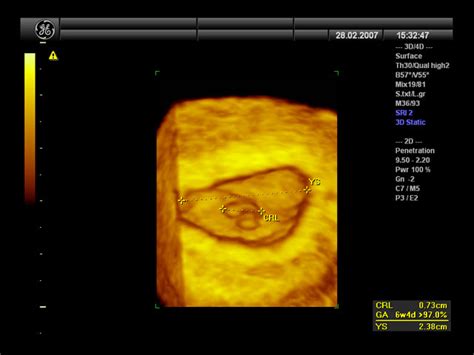

- Prikaz gestacijske vrečke: Z ultrazvočnim pregledom, še posebej s transvaginalnim, je v tem zgodnjem obdobju pogosto že mogoče zaznati gestacijsko vrečko. Ta se prvič pojavi pri približno 4 tednih gestacijske starosti in raste s hitrostjo približno 1 mm na dan. Videti je kot ehogeni obroč, ki obdaja bistro središče. Izvid na ultrazvoku lahko prikaže gestacijsko vrečko (GV) z določenimi merami (npr. 21 mm).

Prvi ultrazvočni pregled po IVF je ključen za potrditev nosečnosti in zgodnje spremljanje razvoja. Običajno se opravi med 7. in 8. tednom nosečnosti (redko že v 6. tednu) na kliniki za zdravljenje neplodnosti. Med pregledom se preverijo:

- Prisotnost, velikost in oblika gestacijske vrečke (ali več gestacijskih vrečk): Pokaže zgodnjo prisotnost nosečnosti.

- Prisotnost in velikost rumenjaka: Rumenjak oskrbuje zarodek s hranili do razvoja posteljice.

- Prisotnost plodovih srčnih utripov: S srcem, ki utripa s hitrostjo 60-90 utripov/minuto, se potrdi vitalna klinična nosečnost.

- Velikost ploda (CRL - Crown-Rump Length): Meritev od glave do zadka omogoča natančno določanje gestacijske starosti. V 6. tednu nosečnosti plod meri okoli 4-6 mm.